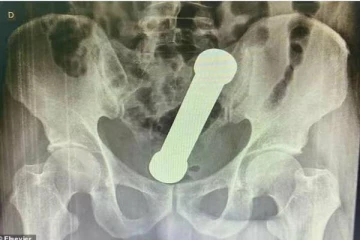

இன்பத்திற்காக முதியவர் செய்த பகீர் செயல்! ஸ்கேன் ரிப்போர்டை கண்டு ஆடிப்போன மருத்துவர்கள் 4 ஆண்டுகள் முன்